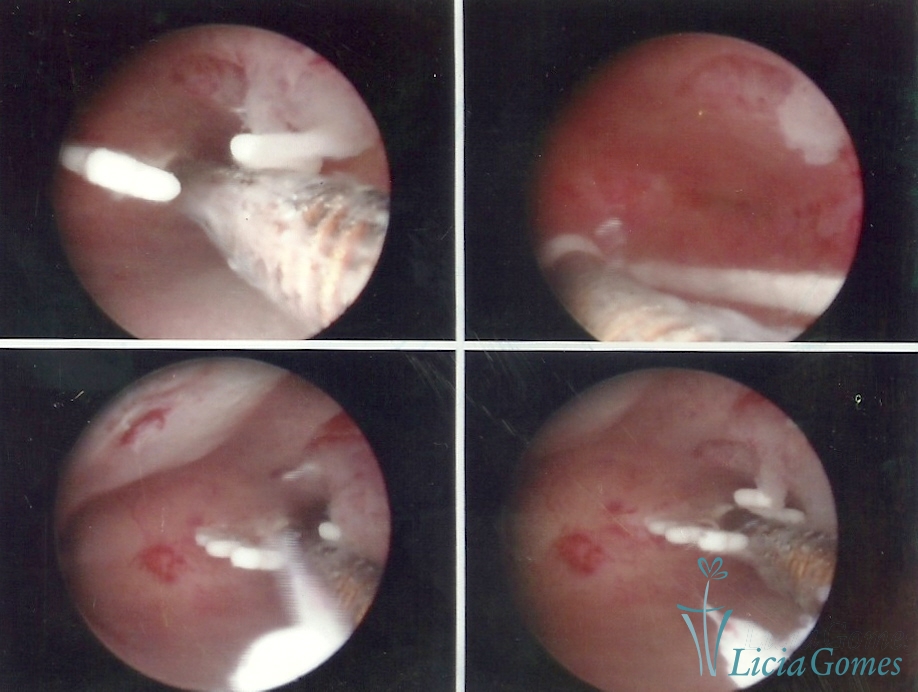

Cesarean section scar with a non-absorbed suture, as a foreign body

×